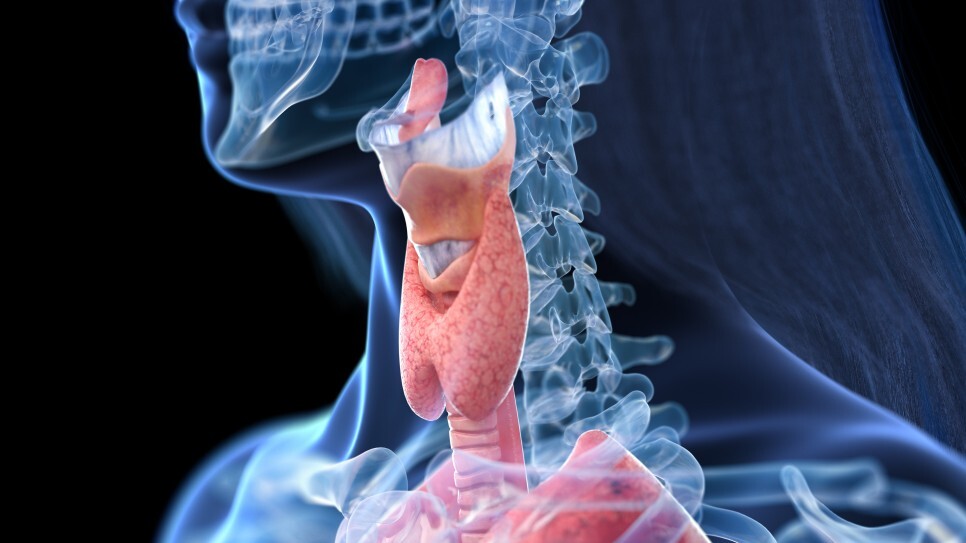

갑상선항진증이란?

갑상선에서는 체온 조절과 신진대사 등에 관여하는 호르몬을 분비하는데요, 어떠한 이유로 과도하게 분비되어 인체 대사가 증진되며 에너지 소모가 일어나게 되는 것을 갑상선 기능 항진증이라 합니다.

원인은?

갑상선항진증의 주된 원인은 자가면역질환인 그레이브스병입니다. 이 외에도 갑상선 호르몬제를 과다 복용한 경우 혹은 갑상선종이나 뇌하수체 선종이 있는 경우 종양에 의해 갑상선 자극 호르몬이 과도하게 분비되어 나타날 수 있습니다.